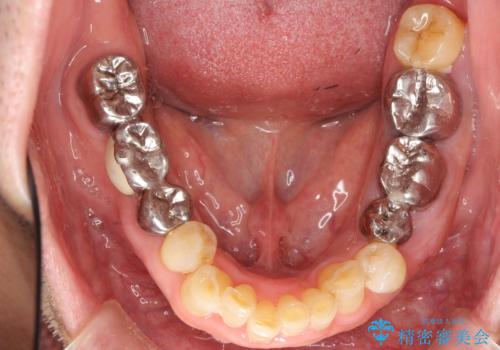

- 左下奥歯の歯ぐきから膿が腫れてきたことを主訴に来院された患者様です。

精査したところ奥歯(左下6)が破折しており、保存不可能と診断されました。

インプラント・入れ歯・自家歯牙移植(親知らずの移植)の選択肢を提案させて頂いたところ、自家歯牙移植をご希望されました。

保存不可能な奥歯(左下6)を抜歯し、機能していない親知らず(左下8)の移植を行いました。